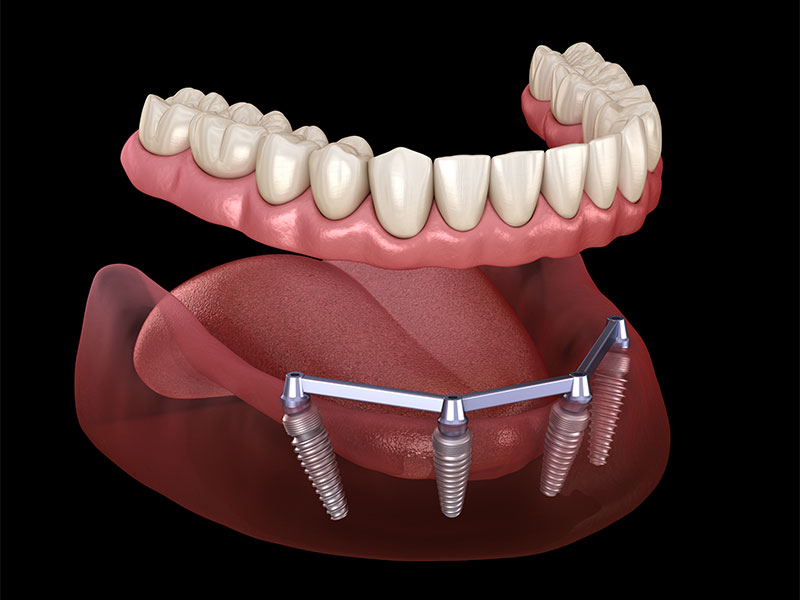

Overdenture su impianti:

protesi totali agganciate ad impianti dentali con attacchi a pressione che consentono la rimozione da parte del paziente. Questa soluzione è realizzabile quando si dispone ancora di una quantità sufficiente di osso mascellare.